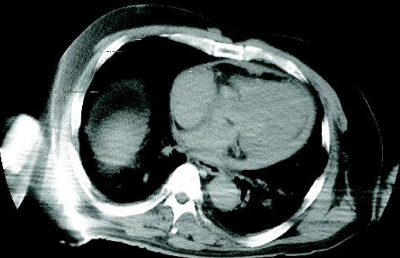

身長 170 cm、体重 90 kg。背面に死斑が高度に発現し、硬直は全身の諸関節で強い。外表に創傷はない。脳は 1,750 g で浮腫状である。胸郭・脊椎に骨折はなく、左右胸膜腔に液体貯留はほとんどない。心囊に破裂はない。心重量は 610 g で冠状動脈に内膜肥厚・血栓はなく、心筋には異状を認めない。大動脈は Valsalva 洞から左鎖骨下動脈起始部の下 15 cm の高さにかけて、内外膜間が解離し、両端部の内膜および中膜に亀裂がある。肺と肝臓はうっ血しているが、臓器表面に異状はない。死後解剖前に撮影した胸部 CT及び解剖時に心囊を切開した際に撮影した写真を別に示す。

《画像:掲載不可》心嚢に血液が溜まっている開胸画像

e. 心タンポナーデ